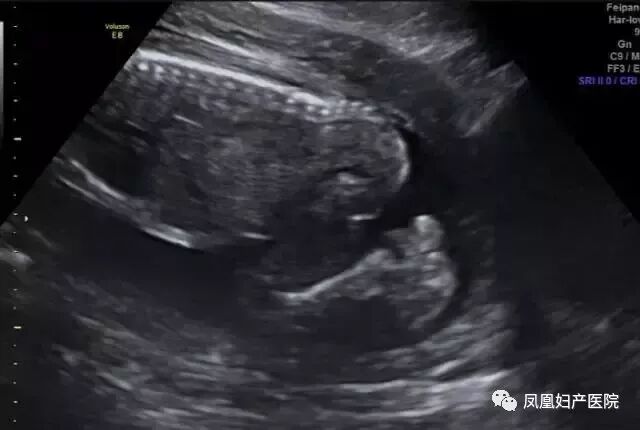

27岁的小美(化名)和相爱多年的男友结婚一年后,一个小生命的悄然到来,给整个大家庭送上了一份惊喜,他们俩感觉太幸福了。然而不幸的事情发生了:小美孕25周超声检查发现胎儿下肢无双腿,双下肢合并外形似鱼尾状,这是一种非常罕见的多发性畸形,双下肢合并外形似鱼尾状,俗称“美人鱼综合症”。

去年一位40岁的二胎妈妈在一次常规的产检中,发现胎儿下肢是两个大腿骨, 并行排列 ,小腿骨好像有点交叉 。正常胎儿的下肢是不停地在妈妈肚子里动的, 呈现一个外八字,后来确诊为美人鱼综合症。因为多数患病的新生儿出生后,只能存活几个小时,就算活下来,也要接受多次手术治疗。